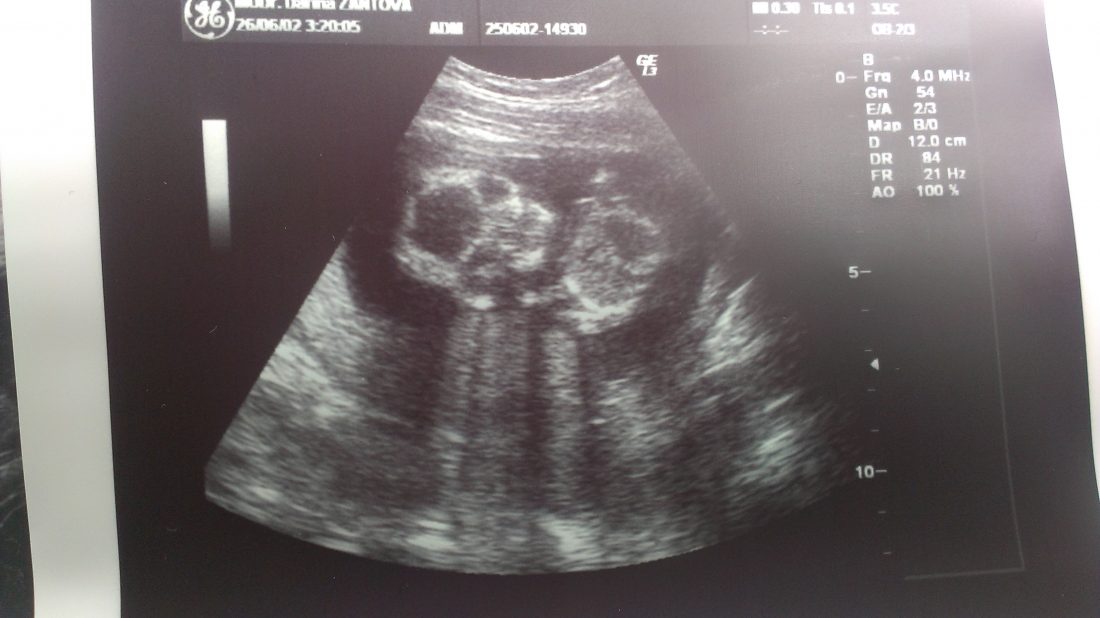

Je to potvrzeno – bude to chlapeček :)